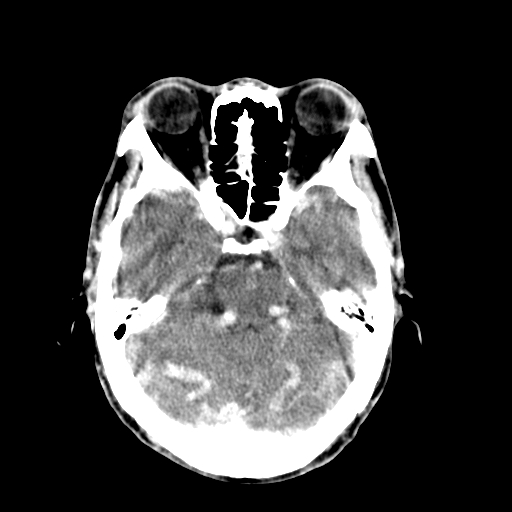

标题: CT17002:M48Y,血管畸形,血管瘤,请鉴赏! [打印本页]

男48y,头痛多年,加重一天!

典型的血管畸形---avm  -----右侧枕顶叶及侧脑室三角区等高混杂密度影夹杂少许低密影显示,无明显水肿,增强可见明显的供血动脉与引流静脉显示